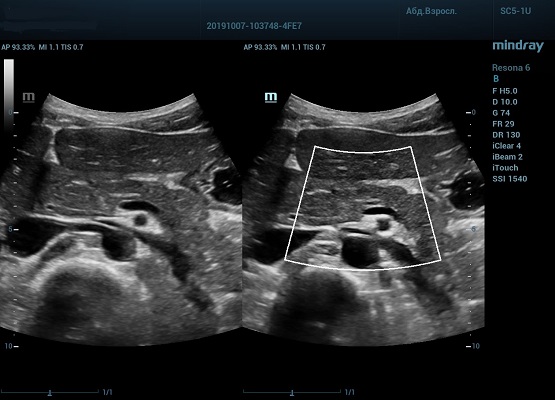

Производители ультразвуковых приборов постоянно работают над облегчением рабочего процесса доктора ультразвуковой диагностики, на этот раз компания Mindray добавила в экспертные и премиум аппараты, такие как Resona 6 и Resona 7, функцию HD Scope.

HD Scope позволяет достигать поразительной разрешающей способности выбранной зоны сканирования, при этом улучшая как детализацию, так и контрастность изображения. Помимо пространственного разрешения мы получаем преимущество и по разрешению во времени. Прибор получает огромное количество нативных изображений практически одновременно, и при сборе итоговой картины не происходит смещения объекта под датчиком, а значит и нет размывания изображения. Все участки раздела фаз, каждый контур образования теперь видны, мы все ближе к идеальной картинке.

Как он работает? Особенностью платформы ZST+, на которой построены приборы Mindray Resona, является так называемое многолучевое сканирование. В отличие от обычного датчика, который получает изображение в виде прямого эхо, датчики приборов этой серии проводят многолучевое сканирование каждым элементом с огромной скоростью, получая огромное количество данных. Затем происходит сложная постобработка и сбор из множества «многолучевых» снимков идеальной картинки.

Вторая особенность ультразвуковых машин данной линейки — это изменение расчетных констант распространения ультразвука, таким образом прибор перебирает для каждой ткани свои значения скоростей волны и пересчитывает каждую точку, делая менее выраженным поглощение по глубине. Эти особенности позволили использовать без фокусные технологии сканирования. Функция HD Scope позволяет использовать эти ресурсы для исследование небольшой области, значительно увеличивая качество изображения.